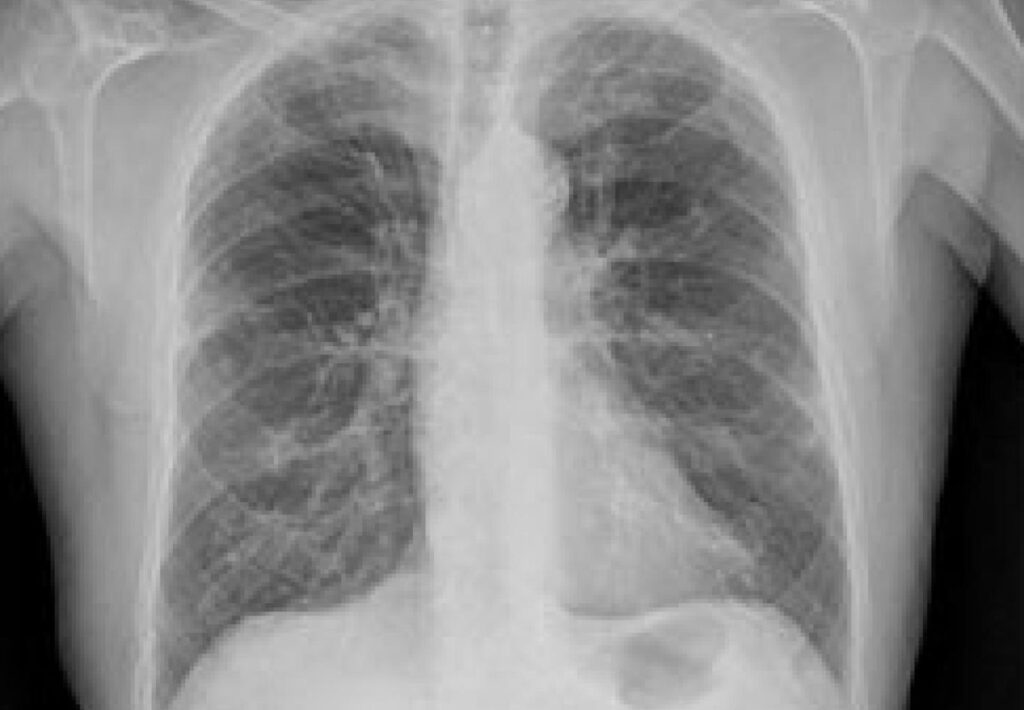

La Enfermedad Pulmonar Obstructiva Crónica (EPOC) es una afección respiratoria progresiva que limita el flujo de aire y provoca síntomas como tos persistente, dificultad para respirar, opresión en el pecho y fatiga.